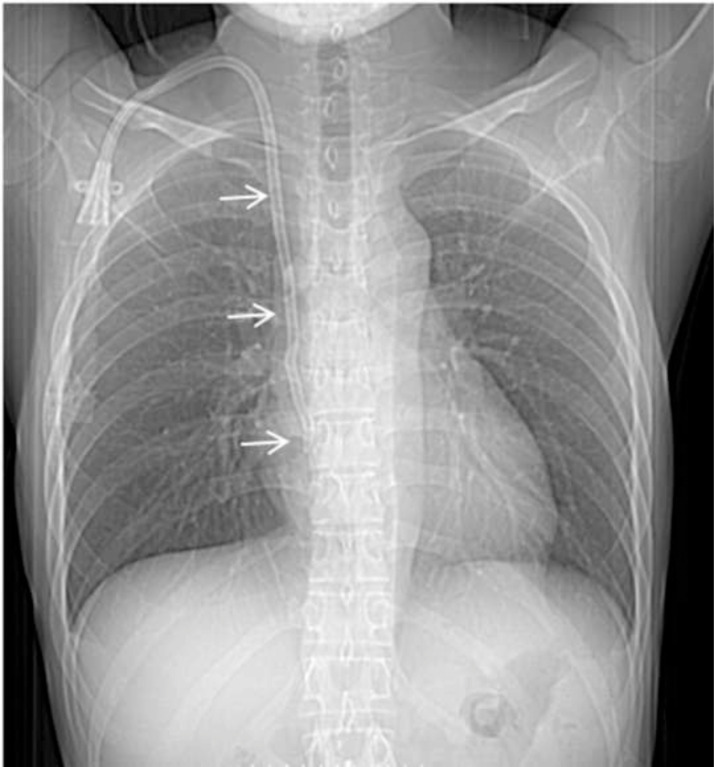

The patient underwent a chest X-ray, which did not reveal any abnormalities (Fig. 1). Abdominal ultrasound and electrocardiogram also revealed no abnormalities. Ultrasonography of the urinary system displayed bilateral renal parenchymal echogenicity. The patient underwent sputum TB tests (direct endoscopy, GeneXpert MTB/RIF) with negative results.

Fig. 1.

Conventional chest radiograph. The chest radiograph appeared normal. A fixed catheter appears on the image near the right atrium, which is used for cyclic hemodialysis (arrow).